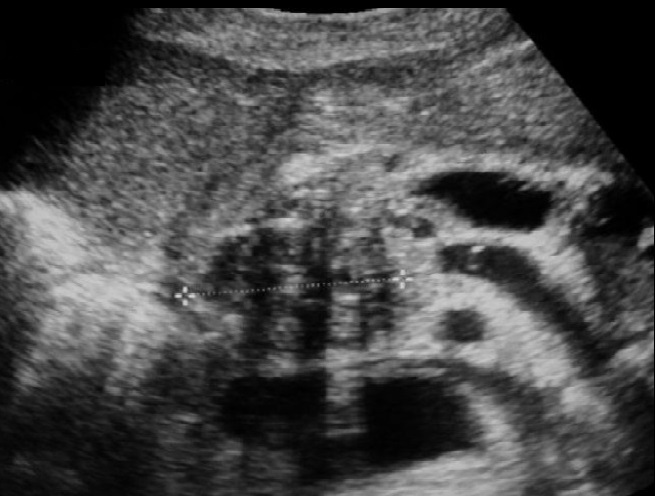

Image echographique indirect de adenocarcinoma de la tete du

pancreas sont : Une dilatation du canal de Wirsung de plus

de 3mm en amont du lesion , dilatation de voie biliaire

principale en associe dilatation des voies biliaires intra

hepatique sur les cas tumeurs cephaliques , une atrophie du

parenchyme pancreatique en amont et un pseudokyste en amont

( pancreatite aigue )